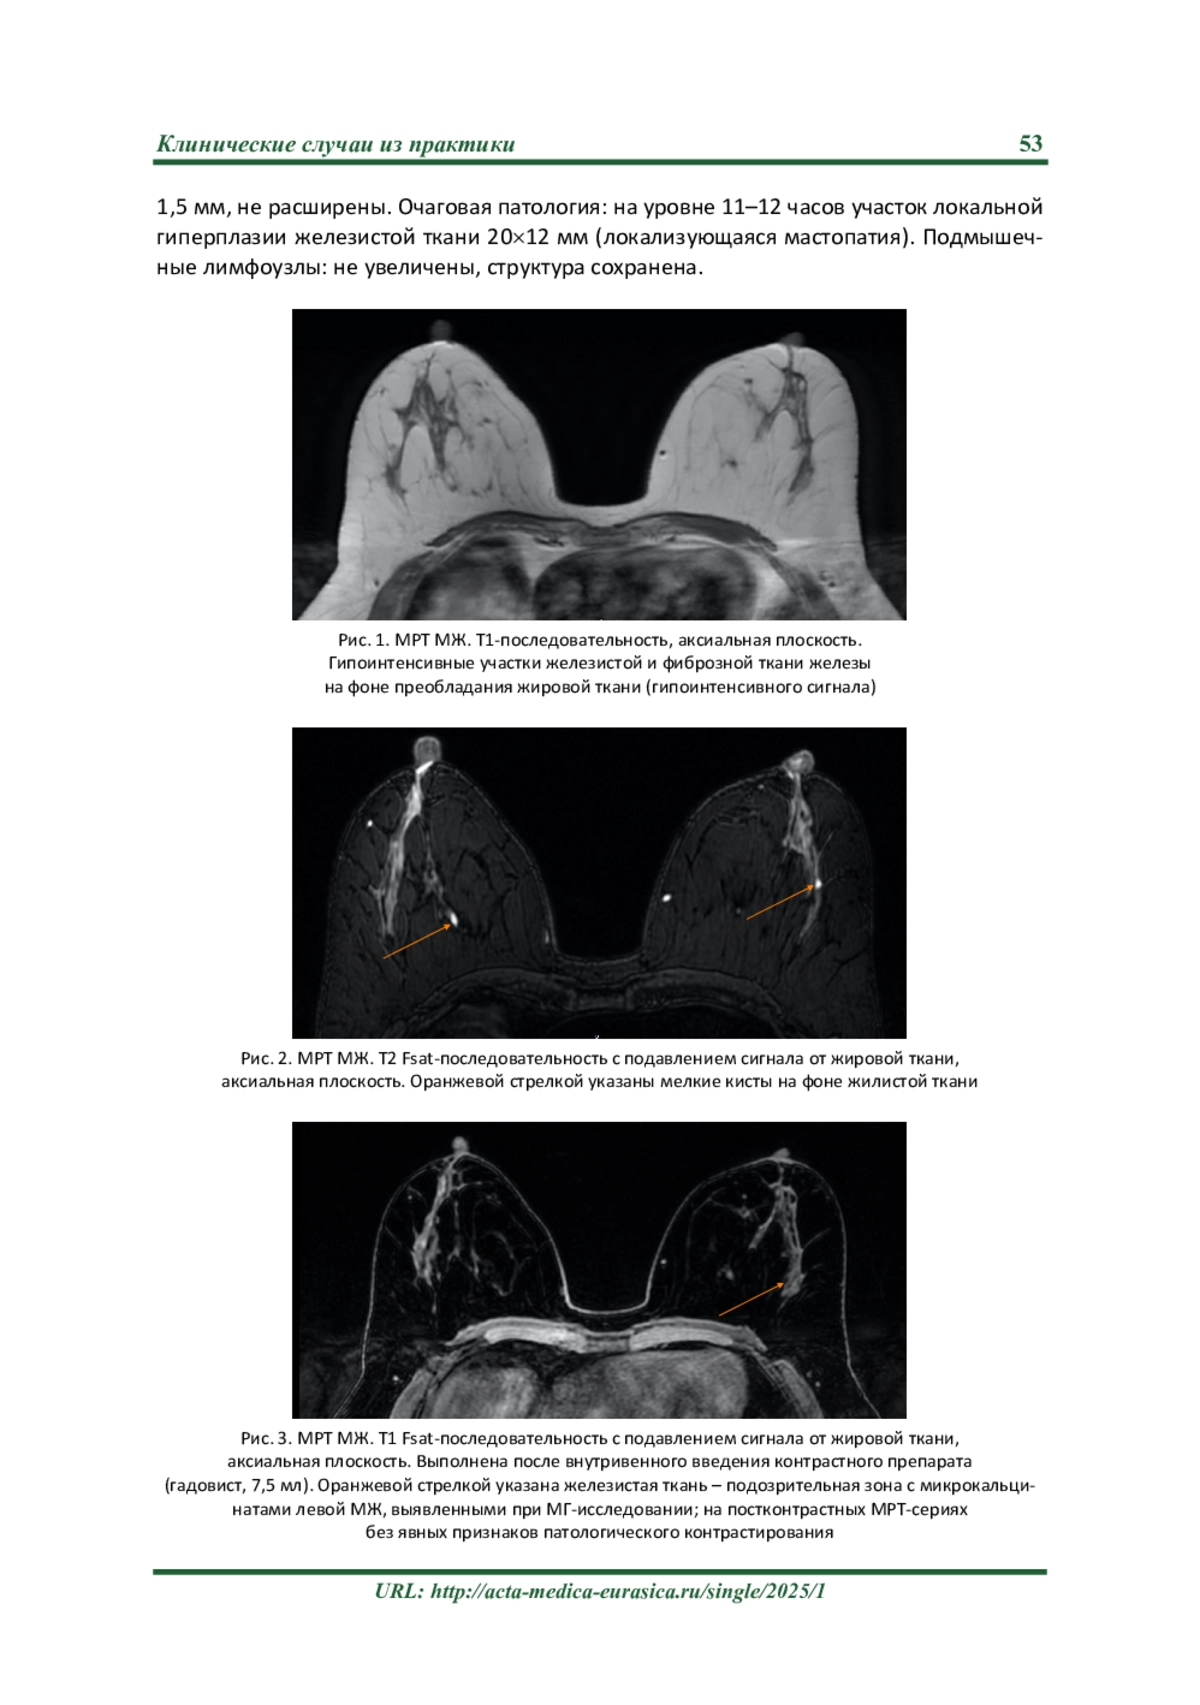

Описание клинического случая. При проведении рентгеновской маммогра‐ фии (РМГ) в рамках первого этапа диспансеризации в поликлинике по месту житель‐ ства у пациентки М., 1970 г. р., обнаружен участок асимметрии ткани левой молочной железы (МЖ) 1724 мм. BI‐RADS 4a в верхнем наружном квадранте. По результатам УЗИ МЖ – зона аденофиброза левой МЖ 147 мм на 12–13 часах, ближе к ареоле. BI‐RADS 3.